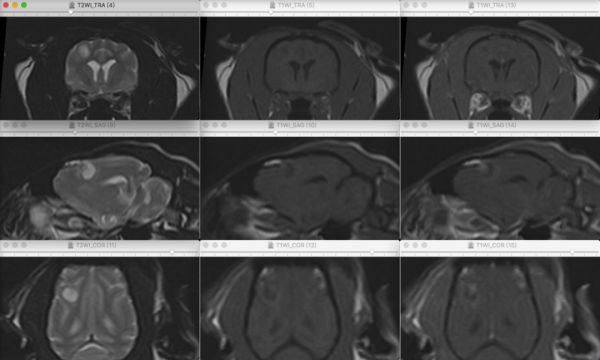

图片图片

猫稳定麻醉状态下,使用 1.5T MRI (SuperVan 1.5T 磁共振成像系统,苏州朗润医疗系统有限公司)对猫的脑部进行扫查,使用顺磁性增强剂(钆喷酸葡胺 Gd-DTPA,0.1mmol/kg,IV)进行增强后扫查,显示颅内多个占位性病变。

主要表现右侧薛氏上沟皮质下、左外侧丘脑,右侧中脑不规则占位性病变,呈 T2WI 高强度信号,T1WI中低强度信号,FLAIR 中高强度信号,伴占位性病变外周轻度至显著不均匀增强,DWI 呈低至无强度信号,脑膜轻度至中度增强信号。

脑中线轻度向右侧偏移,双侧嗅裂和侧脑室轻度扩张,左侧侧脑室轻微受压变形。右侧薛氏上沟灰质下肿物的大小约为6.10mm X 4.59mm X 5.54mm,左外侧丘脑肿物的大小约为12.18mm X 7.91mm X 12.28mm,右侧中脑肿物的最大横截面大小约为9.82mm X 8.86mm X 10.09mm(使用DICOM看图软件 Horos v 3.3.5 在 T2WI 图像上进行测量,软件来源https://horosproject.org)。

正中矢状面可见小脑显著变形,小脑向后位移,小脑尾侧向枕骨大孔疝出,与左侧下行性大脑幕疝和小脑枕骨大孔疝一致。正中矢状面还可见颈部脊髓大面积T2WI 高强度信号,T1WI 低至无强度信号,无增强区域,与脊髓空洞症一致。没有发现其他明显的病变,筛骨气房或筛状板未见异常。

鉴别诊断怀疑肉芽肿性脑病和弥散性肿瘤性病变,主要怀疑真菌性肉芽肿,淋巴瘤,胶质瘤,脑膜瘤,肉芽肿性脑膜脑炎等。

图 1 该病例的脑部 MRI 图像,选取自右侧薛氏上沟灰质下肿物最大横截面所在层,侧脑室轻度扩张,肿物呈 T2WI 中高至高强度信号,T1WI 中等至中低强度信号,伴病变外周轻度至中度增强。从左向右依次为T2WI,T1WI和增强后T1WI。T1WI,T1 加权成像;T2WI,T2 加权成像;TRA,横断面;SAG,矢状面;COR,冠状面。

图 2 该病例的脑部 MRI 图像,选取自左外侧丘脑肿物最大横截面所在层,侧脑室和第三脑室轻度扩张,肿物呈 T2WI 中高至高强度信号,T1WI 中低强度信号,伴外周轻度至中度增强。从左向右依次为T2WI,T1WI和增强后T1WI。T1WI,T1 加权成像;T2WI,T2 加权成像;TRA,横断面;SAG,矢状面;COR,冠状面。

图 3 该病例的脑部 MRI 图像,选取自右侧中脑肿物最大横截面所在层,肿物呈 T2WI 中高至高强度信号,T1WI 中低强度信号,伴病变外周轻度至中度增强。同时可见小脑前侧受肿物挤压向后位移,小脑尾侧向枕骨大孔位移,超出了枕骨大孔并挤压延髓和第一颈部脊髓段,与下行性经幕疝和小脑枕骨大孔疝一致。从左向右依次为T2WI,T1WI和增强后T1WI。T1WI,T1 加权成像;T2WI,T2 加权成像;TRA,横断面;SAG,矢状面;COR,冠状面。

图 4 该病例脑部三处肿物MRI的横断面 FLAIR序列,T2*序列和 DWI 序列。FLAIR,液体衰减反转恢复序列;DWI,弥散加权成像;TRA,横断面;SAG,矢状面;COR,冠状面。